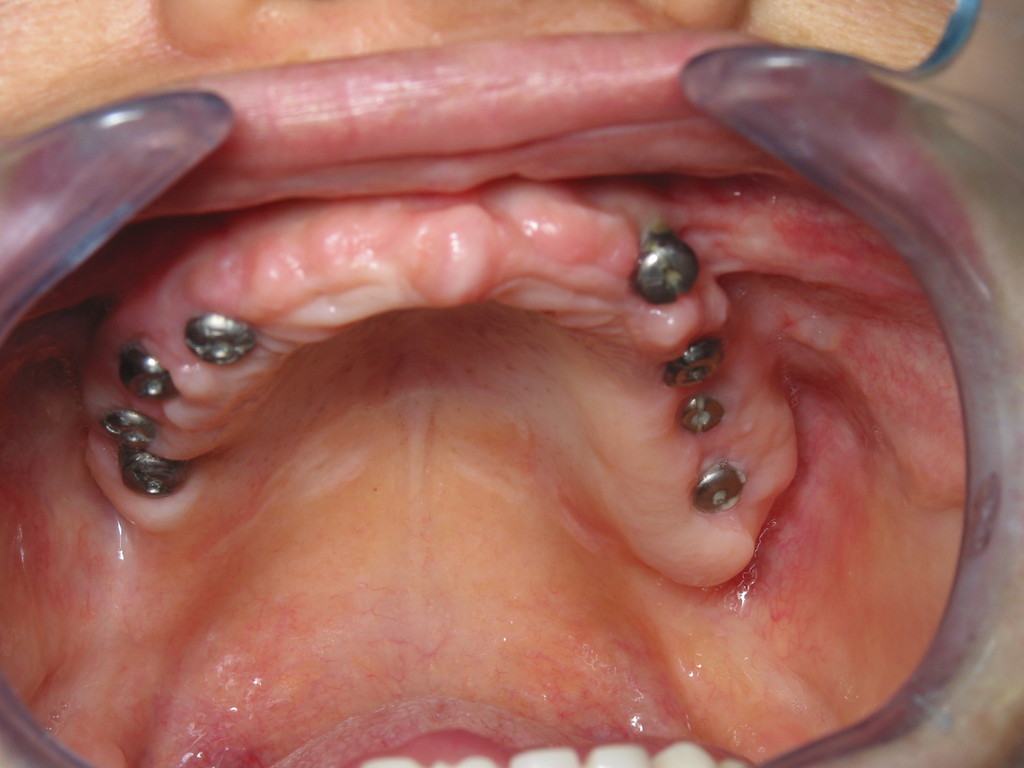

REHABILITACIÓN DE AMBOS MAXILARES CON MESOEXTRUCTURA SOBRE IMPLANTES.

CASO CLÍNICO REHABILITACIÓN CON MESOEXTRUCTURA FIJA EN MAXILAR SUPERIOR Y REHABILITACIÓN CERÁMICA EN MAXILAR INFERIOR EN PACIENTE CON PERIODONTITIS AVANZADA DEL ADULTO

MESOEXTRUCTURA EN PACIENTE CON ENFERMEDAD PERIODONTAL.